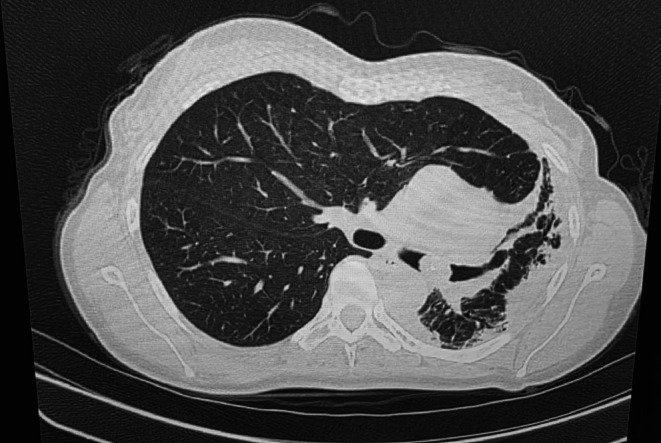

支气管内脂肪瘤是一种罕见的良性肿瘤,起源于支气管壁粘膜下脂肪,占所有肺部肿瘤的不到0.5%。这些肿瘤可表现为非特异性呼吸道症状,通常类似于常见的肺部疾病,如哮喘、慢性阻塞性肺病或感染,这使得诊断具有挑战性。我们提出的情况下,54岁的女性吸烟者谁经历了三个月的历史慢性生产性咳嗽,呼吸困难和反复呼吸道感染。在此期间,她接受了三名医疗服务提供者的评估,根据支气管炎或慢性阻塞性肺病加重的推定诊断,每个人都开了多个疗程的抗生素和吸入支气管扩张剂。值得注意的是,在初始阶段没有进行胸部成像。胸部影像显示左肺萎陷,支气管镜检查显示息肉样肿块阻塞左主支气管。组织病理学分析证实了支气管内脂肪瘤的诊断。本病例强调了在鉴别诊断慢性呼吸系统疾病时考虑良性支气管肿瘤的重要性,特别是在有吸烟史的患者中。完全切除,无论是支气管镜或手术,是治疗的选择,导致良好的预后和症状解决。

Endobronchial lipomas are rare, benign tumours that arise from the submucosal fat of the bronchial wall and account for less than 0.5% of all lung tumours. These tumours can present with non-specific respiratory symptoms, often mimicking common pulmonary conditions such as asthma, COPD, or infections, making diagnosis challenging. We present the case of a 54-year-old female smoker who experienced a three-month history of chronic productive cough, dyspnea and recurrent respiratory infections. During this period, she was evaluated by three healthcare providers, each of whom prescribed multiple courses of antibiotics and inhaled bronchodilators based on presumed diagnoses of bronchitis or COPD exacerbation. Notably, no chest imaging was performed at the initial stages. Chest imaging revealed left lung collapse, and bronchoscopy revealed a polypoidal mass obstructing the left main bronchus. Histopathological analysis confirmed the diagnosis of an endobronchial lipoma. This case highlights the importance of considering benign bronchial tumours in the differential diagnosis of chronic respiratory complaints, especially in patients with a smoking history. Complete excision, either bronchoscopic or surgical, is the treatment of choice, resulting in excellent prognosis and symptom resolution.